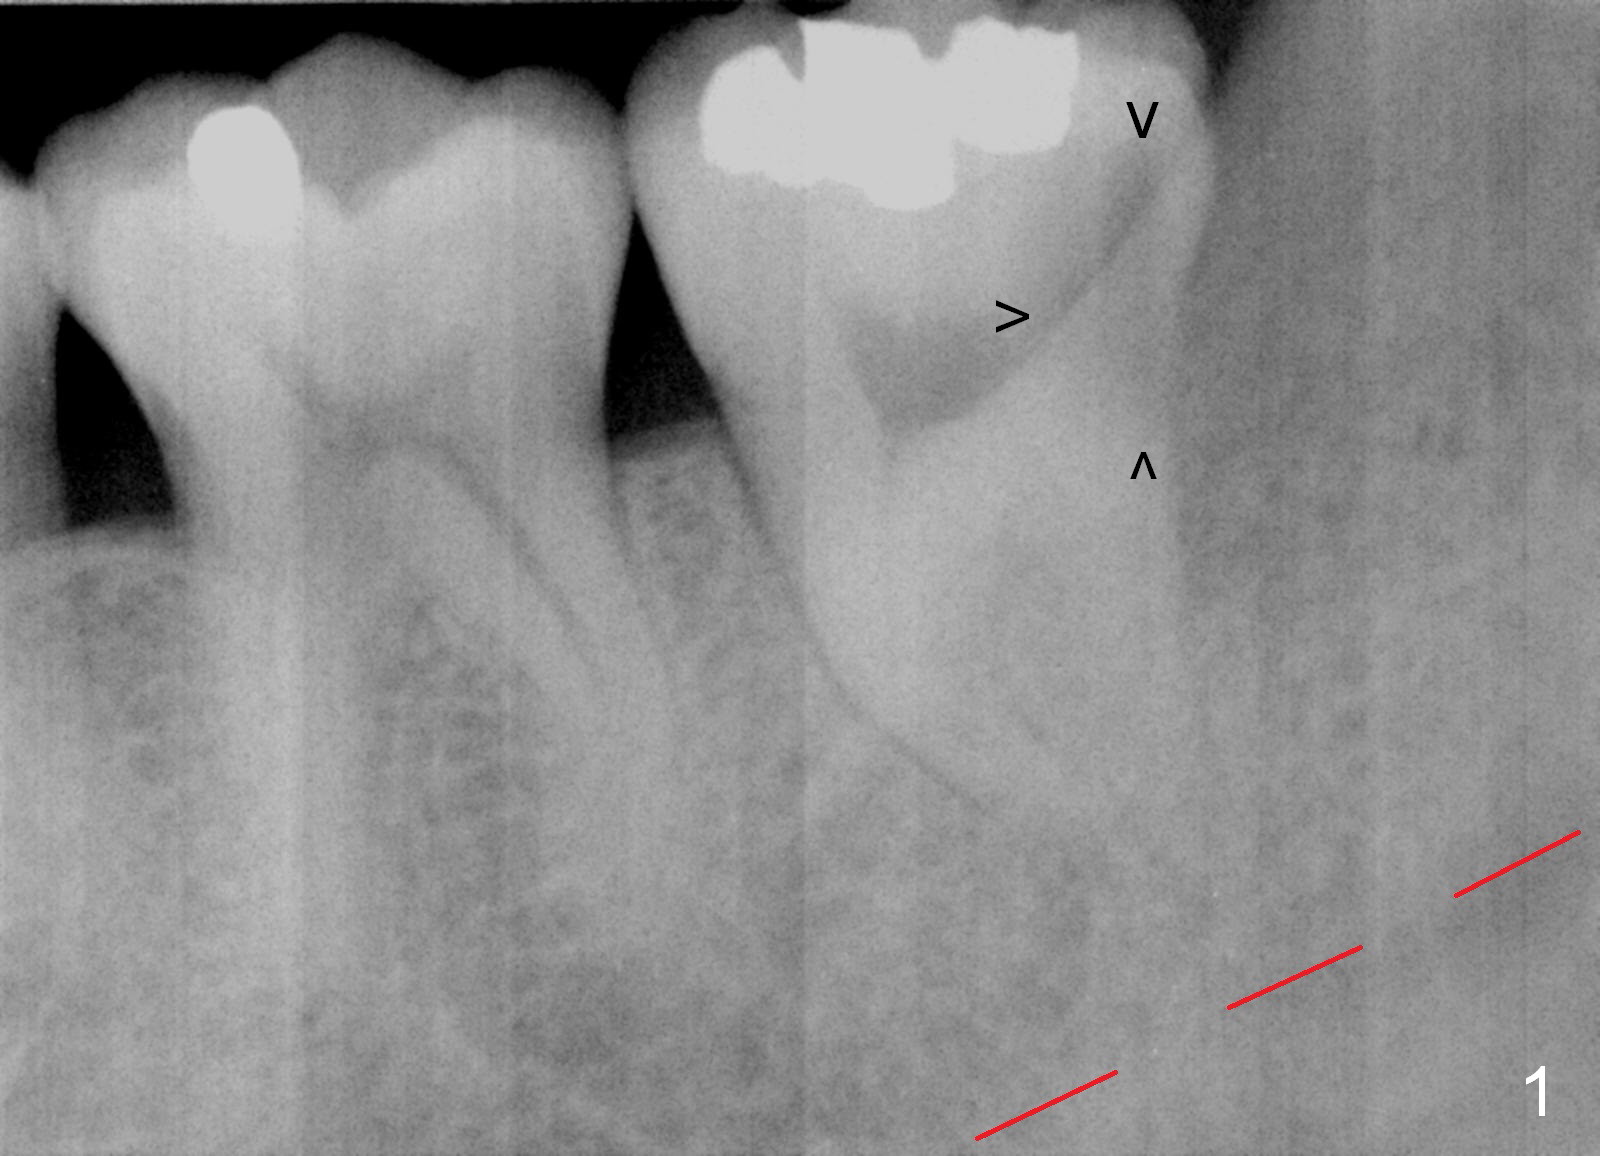

A 34-year-old man has distal deep caries of the lower 2nd molars. Root canal therapy turns out to be difficult on the right side due to bleach leakage. It would be also difficult to restore the distal defect. Finally he agrees to have extraction and implant. The result is good. He is ready to accept the same treatment for the left 2nd molar (Fig.1 (arrowheads: caries)). Metronidazole will be used for socket decontamination. Place a 5.9x10 mm bone-level implant 2 mm below the mesial crest (hopefully at the same level of the buccal crest) so that there is enough height to place an abutment (Fig.2). The apex of the implant is placed mesial to that of the root, since there is more bone, away from the superior border of the Inferior Alveolar Canal (red dashed line). The osteotomy is to be initiated in the middle of the mesial slope obliquely, more mesial (Fig.3 red line) than the center of the implant (green arrow). Once the lamina dura is penetrated, change the trajectory along the future long axis of the implant (Fig.4 red line). The depth will be 14 mm from the mesial gingival line (Fig.2). As the diameter of drills increases, the osteotomy tends to shift distal (Fig.5 pink arrow).